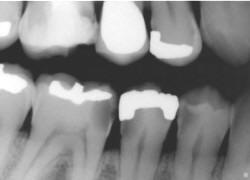

La información radiográfica contribuye significativamente a los hallazgos clínicos en términos del hallazgo de lesiones en diferentes estadíos de progresión (29,32) Las radiografías ayudan a estimar la profundidad de desmineralización por caries en el esmalte y la dentina. La profundidad no siempre está asociada con la presencia de cavidad de caries, en especial en superficies proximales.

Investigaciones clínicas que se realizaron en un país con una tasa baja de progresión de caries revelaron que, en promedio, el 32% de las lesiones visibles radiográficamente que se extendían hasta el tercio externo de la dentina no  había cavidad de caries; por el contario, el 72% de las lesiones que se extendían hasta 2/3 partes de la dentina tenían cavidad de caries (33) Las lesiones con cavidad de caries clínicamente o las lesiones con obvia radiolucidez en dentina (más profunda que el 1/3 externo) en la superficie oclusal están altamente infectada la dentina, debajo de la unión amelo-dentinaria (34,35)

Si las radiografías están disponibles, el primer paso es clasificar las lesiones de caries coronal en dientes posteriores de acuerdo con los grados que están en la Tabla 4.

Sistema radiográfico ICDAS  (Radiografía Bite-Wing)

Sano

R0 No hay radiolucidez

Estadios iniciales *

RA1 Radiolucidez en 1/2 externa del esmalte

RA2

Radiolucidez en la 1/2 interna del esmalte ± UAD (Unión amelo-dentinaria)

Se lo considera aún un estadio inicial porque no hay dentina infectada )

RA3 Radiolucidez limitada al 1/3 externo de la dentina

Estadio moderado

(En este estadió comiemza la infección de la dentina por bacterias orales)

RB4 Radiolucidez que alcanza hasta el 1/3 medio de la dentina

Estadios severos

(Infección franca de la dentina)

RC5 Radiolucidez que alcanza hasta el 1/3 interno de la dentina, clínicamente cavitada

RC6 Radiolucidez en la pulpa, clínicamente cavitada

* Nota- La mayoría de lesiones confinadas al esmalte no se ven en las radiografías.

Tabla 4: Clasificación radiográfica ICDAS

El ICCMS clasifica radiográficamente las superficies posteriores de los dientes (36,37)  Se ha reportado que tanto la reproducibilidad como la precisión de este sistema de clasificación son de significativas (33) a excelentes (37)

La evidencia indica que la profundidad de penetración radiográfica en la que se puede predecir de forma confiable que la superficie del diente está cavitada y que la dentina está muy infectada, es cuando la radiolucidez está más alla del tercio externo de dentina (7,34,35,38,40). Esto corresponde a los códigos 4, 5 y 6 en el sistema de clasificación radiográfica de ICCMS. Ver tabla 6. En casos en que las tasas de progresión son rápidas, se puede esperar que en lesiones con clasificación 3 en el sistema descrito anteriormente, haya formación de cavidad.